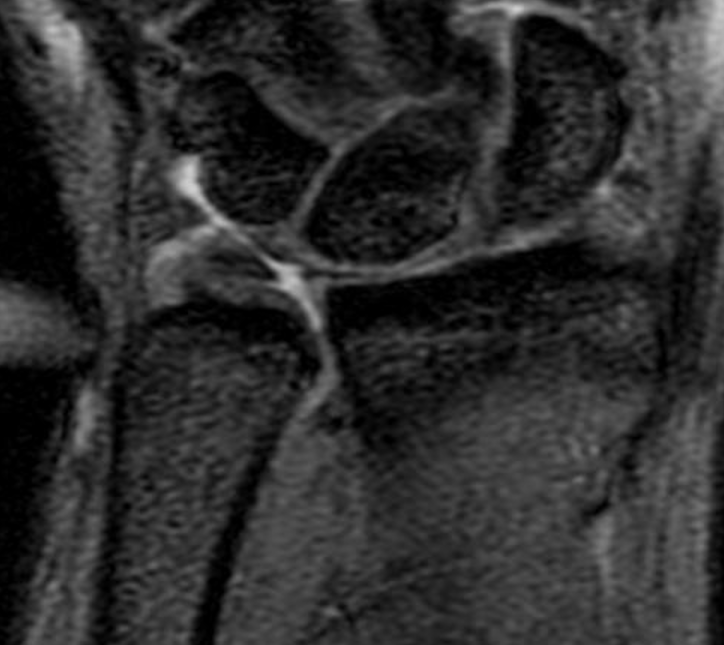

TFCC tears

Ulna sided tear

Radial sided TFCC tear

Central TFCC tear